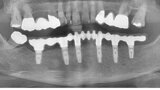

Počítačem asistované, šablonou se řídící okamžité zavedení a zatížení implantátu v dolní čelisti